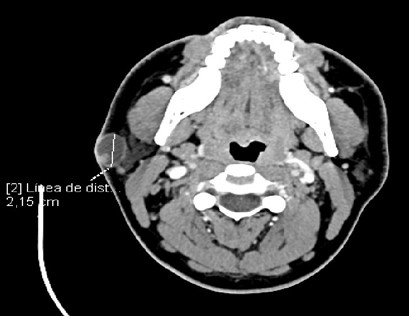

The CT scan of the neck with intravenous iodinated contrast revealed an oval image measuring 21 x 16 x 24 mm (AP x T x CC) located in the subcutaneous tissue at the level of the mandibular angle and the tail of the right parotid gland, superficial to the deep cervical fascia. It presented hypodense contents (probably cystic), with a thin, hyperenhancing wall and a small, 7 x 5 mm intraluminal hyperdense image adjacent to its posterolateral wall. The findings were suggestive of a soft tissue tumor, but radiologically nonspecific. No pathologically apparent laterocervical lymphadenopathy was observed.

Imagen 2: axial CT scan shows a nodule on the right side at the level of the mandibular angle.